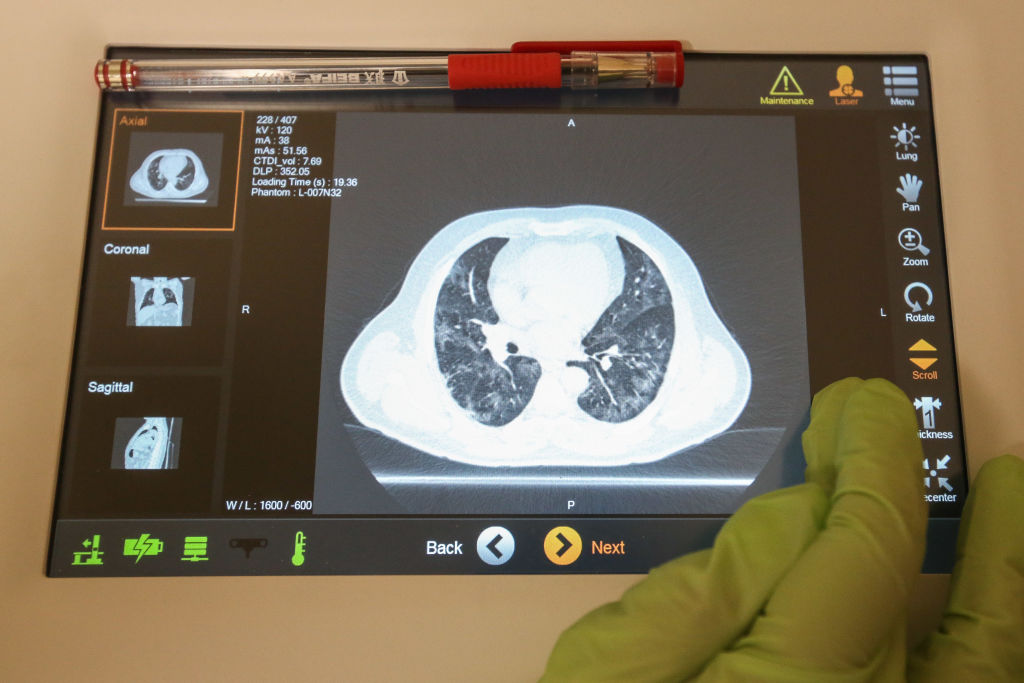

La detección temprana del cáncer, de cualquier tipo, es clave para acceder a un tratamiento a tiempo. Por ejemplo, si eres un fumador de mucho tiempo o estuviste cerca de uno, puedes hacerte una prueba de detección.